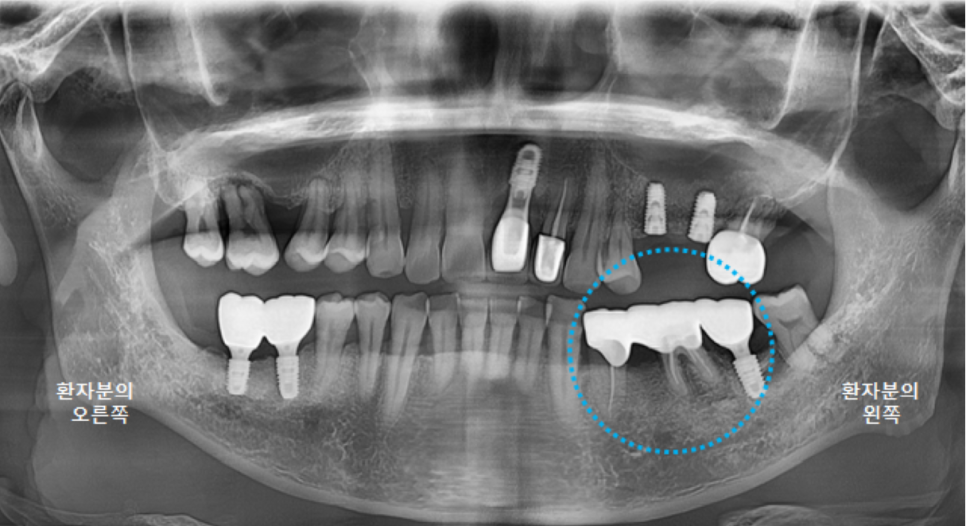

전체적인 구강 판단을 위해

파노라마 엑스레이 사진을 찍었습니다.

왼쪽 큰앞니도 빠져있지만,

오른쪽위 큰어금니, 오른쪽 아래 큰어금니도 발치된 상태였고,

왼쪽 위 브릿지 상태도 좋지는 않았습니다.

왼쪽 아래 큰어금니 하나는 뿌리만 남은 상태였어요.

앞니 임플란트 수술 직후 파노라마 엑스레이 사진입니다.

양옆의 치아 관계도 좋고 뼈이식도 잘 되었습니다. ^^